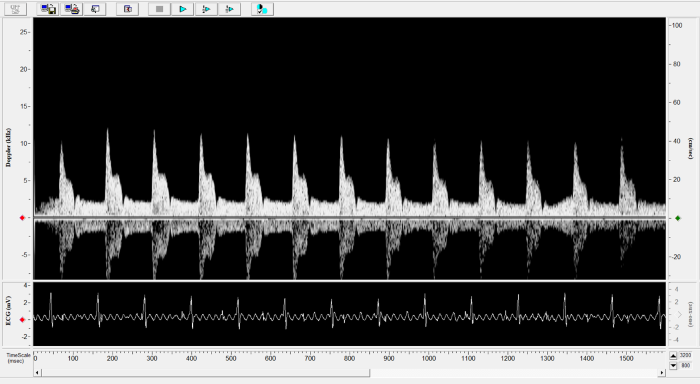

Imaging gallery - Doppler Flow Velocity System

Carotid Image. Image Credit: Scintica Instrumentation Inc.

Renal Flow. Image Credit: Scintica Instrumentation Inc.

Pulmonary Flow. Image Credit: Scintica Instrumentation Inc.

Mouse - Abdominal Aorta. Image Credit: Scintica Instrumentation Inc.

Mouse - TAC Procedure Imaging. Image Credit: Scintica Instrumentation Inc.

Mouse - Coronary Flow Reserve Imaging. Image Credit: Scintica Instrumentation Inc.

Rat - Left Carotid. Image Credit: Scintica Instrumentation Inc.

Rat - Transverse Aorta. Image Credit: Scintica Instrumentation Inc.

Rat - Right Carotid. Image Credit: Scintica Instrumentation Inc.

Rat - Abdominal Aorta. Image Credit: Scintica Instrumentation Inc.

Mouse - Left Anterior Descending Coronary Artery. Image Credit: Scintica Instrumentation Inc.

Mouse - Left Carotid. Image Credit: Scintica Instrumentation Inc.

Mouse - Mitral Inflow. Image Credit: Scintica Instrumentation Inc.

Mouse - Ascending Aorta. Image Credit: Scintica Instrumentation Inc.